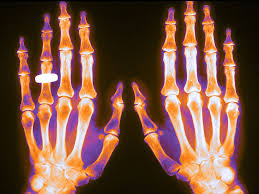

JAMA, 17 de enero de 2017 Las fracturas debidas a la osteoporosis representan un serio y costoso problema de salud pública, que conduce a la discapacidad y a un mayor riesgo de mortalidad. Para las mujeres posmenopáusicas, las fracturas osteoporóticas son más comunes que el ictus, el infarto de miocardio y el cáncer de mama combinados.